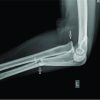

A 4-year-old male presented in our outpatient clinic with a long arm splint at the day after his fall. At first, his parents had taken him to another hospital where he has given the initial treatment as closed reduction and long arm splint. In our examination, capillary refill was good, there was no sign of compartment syndrome. The family was informed that the child might have the diagnosis of Monteggia fracture but we could not reach the radiographs. We took true radiographs of both arms (Fig. 1) to look for any other pathology involving elbow and wrist joints. Both forearm bones were fractured and radial head was still dislocated laterally, despite the reduction done in the first attended clinic. In Monteggia fracture dislocation, lateral dislocation of radial head is typically seen with ulna fracture in Bado type 3 while both bone forearm fracture normally exists with anterior displacement of radial head in Bado type 4 [2]. The Bado classification system is primarily based on the direction of radial head dislocation. Therefore, we considered it as a Monteggia type III equivalent lesion and planned to do closed reduction with or without internal fixation under general anesthesia.